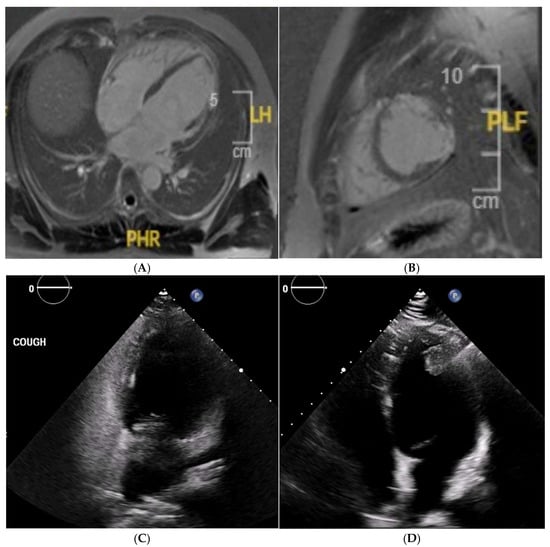

The cardiac MRI acquisition should include standard long-axis and short-axis cine stacks, phase-contrast sequences of the aortic and pulmonary root, and post-contrast sequences [105,106]. These sequences provide a comprehensive morpho-functional evaluation of the mitral valve and subvalvular apparatus, including localising prolapsing segment/s, prolapse severity, leaflet thickness, papillary muscle anatomy, and MAD and MR quantification. CMR has been found to be more sensitive to identifying MAD compared to transoesophageal echocardiography and transthoracic echocardiography [107]. Additionally, cardiac MRI aids in identifying anterior MVP, as it directly correlates with non-ischaemic fibrosis of the papillary muscles and LV inferolateral basal segment (Figure 9). Both of these are linked to prolapsed leaflets and annulus hypermobility [108]. In cases of minimal MR, cardiac MRI may reveal a disproportionate LV remodelling and fibrosis associated with malignant arrhythmias, facilitating the identification of athletes at elevated risk [104]. Further, there is emerging evidence of the role of cardiac MRI in identifying myocardial ECV through T1 mapping. Studies have demonstrated that ECV is increased in MVP patients with MAD compared to those without MAD and MR or isolated MVP [108]. Moreover, MVP patients who have sustained out-of-hospital cardiac arrest exhibit a higher ECV and LGE [30].

Figure 9. A 42 year old Caucasian male, engaging in power sport (recreational) for 20 years, presented with a profound drop in exercise tolerance. Murmur heard on physical examination. T-wave inversion in the inferior leads noted. Supraventricular arrhythmias during an exercise test. Mitral valve (MV) prolapse with moderate regurgitation noted on echocardiogram. Cardiac MRI showed a dilated LV, an LV ejection fraction of 58%, and mitral annular disjunction (arrow) (A). There was prolapse of the posterior MV leaflet with moderate regurgitation (B). Post-contrast imaging identified a subepicardial scar in the lateral wall (arrow) (C,D), consistent with a diagnosis of malignant MV prolapse. He was subsequently referred for MV surgery.